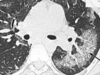

A

Patrón intersticial reticular